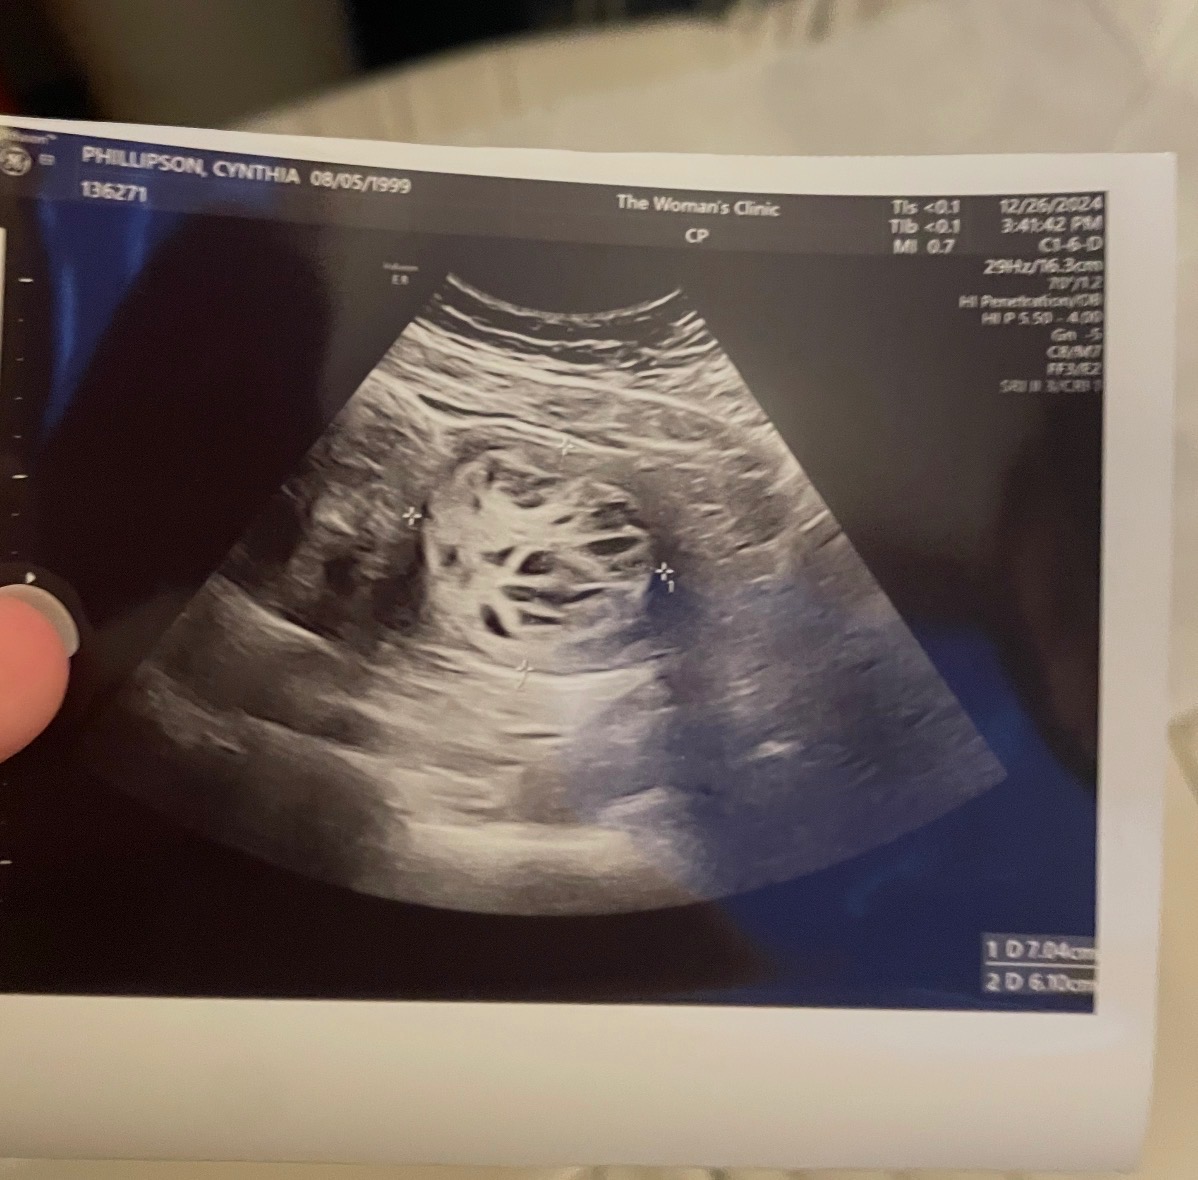

Hi, my name is Andrea Carter. I want to share my sister’s story. Cynthia Phillipson is 26 years old and has been with her husband, Blake Phillipson, for 8 years and married for 6 years. She has always dreamed of having children but unfortunate news after another, she has not yet had the chance. She has unfortunately been diagnosed with PCOS. Blake and Cynthia have been praying for a child for more than 5 years now. In May of 2024, just over a year ago, Cynthia had a laparoscopic surgery to drain a large cyst off of her uterus. The cyst was over 12cm long and 10cm wide. Her cycle did not come back after this surgery and after 5 months, she was left with the same agonizing back pain as before. By November of 2024, Cynthia was back at the doctor’s office again wondering if something had gone wrong. Her obgyn thought maybe something more was going on that they weren’t able to see on a sonogram and sent her to get an MRI. She was also referred her to a specialist oncologist obgyn. Cynthia went back and saw Dr. Daily on February 14, 2025 and got her results. She had a large tumor in her uterus which appeared to have some cancerous tissue. By March of 2025, she had an open abdominal myomectomy surgery to remove the new tumor and cyst. Cynthia was warned that if tests done on the samples showed clear signs of cancer, she would have a hysterectomy during the surgery. She had no idea the outcome of the surgery until she woke up and could think clearly. The results of the surgery listed the tumor as a “stump”, uterus in tact, 35 staples, and 6 weeks minimum bed rest to heal properly. Cynthia is still healing from this procedure. She was told to come back for a CT scan in 6 months and at 12 months she could start trying for a baby again! October of 2025 she had her CT and it shows she has a mass on her lung as well as the tumor seems to regrown in her uterus. Not long after she got a MRI to see more. On October 31st, Cynthia found out that the tumor had in fact come back, but this time in only 6 months. We all feared this outcome because unfortunately, she will have to be reopened for a hysterectomy. They will test the tumor to see if it’s cancerous or benign. It is such devastating news for her. Finding out news like that at only 26 years old has caused so much pain for her.